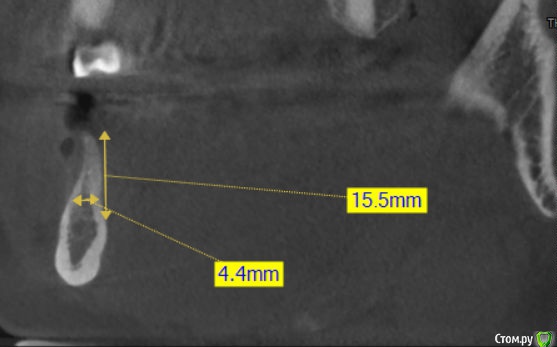

Kazankov.Egor Опубликовано 26 декабря, 2018 Поделиться Опубликовано 26 декабря, 2018 Прислал ортопед, зона 46. Смущает малое количество губчатого вещества и возраст предпенсионный (по старому варианту). Хотелось бы услышать мнение опытных коллег. Ссылка на комментарий

Kazankov.Egor Опубликовано 26 декабря, 2018 Автор Поделиться Опубликовано 26 декабря, 2018 (изменено) а что смущает? голосую за "сосиску" Смущает что в зоне сосиски/нкр мало губчатого вещества, много кортикалки, раньше в таком раскладе у меня получался остеоид, который мало напоминает кость (мало крови). Второе вытекает из первого, сколько графта "прорастает" по толщине при таком донорском ложе? Изменено 26 декабря, 2018 пользователем Kazankov.Egor Ссылка на комментарий

Kazankov.Egor Опубликовано 29 декабря, 2018 Автор Поделиться Опубликовано 29 декабря, 2018 Язычная стенка держит высоту. Методика регенерации зависит и от биотипа слизистой, и от протяжённости дефекта, и от опыта. Плюс декортикация (боры, скребок..)примерно на сколько можно утолщить? Ссылка на комментарий

pit Опубликовано 30 декабря, 2018 Поделиться Опубликовано 30 декабря, 2018 примерно на сколько можно утолщить?Достаточно чтобы получилось 8мм по горизонтале для стандартной платформы имплантата. 1 Ссылка на комментарий

Nazim_NV86 Опубликовано 2 января, 2019 Поделиться Опубликовано 2 января, 2019 Смущает что в зоне сосиски/нкр мало губчатого веществаКажется там его вполне достаточно. Ссылка на комментарий